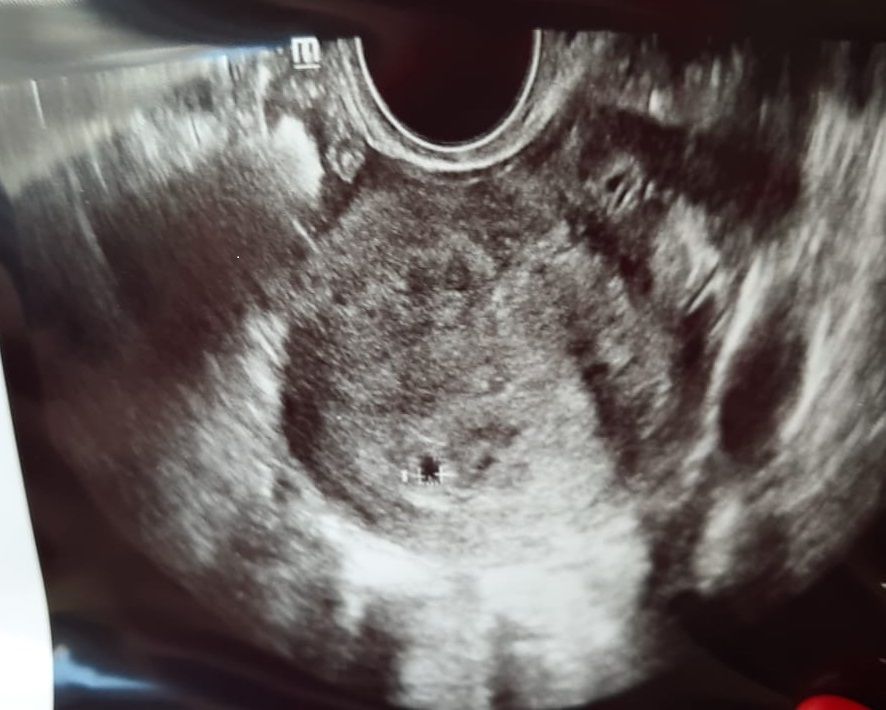

Беременность подтверждена УЗИ) 4нед 6 дн

Была сегодня у гинеколога. Она сказала идти подтверждать маточную Б в ближайшие дни, а СБ слушать спокойно через пару недель. Поэтому сразу пошла на УЗИ) ПЯ нашли в полости матки. И два желтых тела. В первую Б была такая же история, но эмбриончик, в итоге, был один. Посмотрим, как будет в этот раз) Знаете, теперь мне гораздо спокойнее. Всем "односрочницам" удачи) Рассказывайте, как у вас проходит все?

Натик, по узи только вот так написано

В верхней трети полости матки визуализируется плодное яйцо средним внутренним диаметром 0,35 см.

И врач и узист сказали,что все ок и отпустили гулять. ХГЧ не сдавала, хотя все ДМС оплатили. Лень мне просто) Все будет хорошо, не переживайте! Вообще, нужно меньше читать и сравнивать. На таких сроках все очень по-разному у всех проходит)